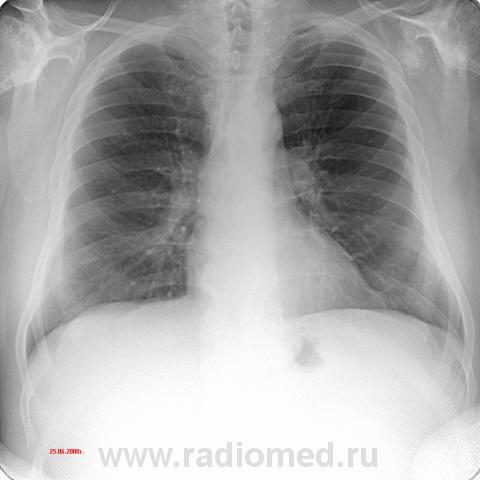

Пациент 60 лет, при прохождении проверочной флюорографии  обнаружены изменения со сторны плечевых суставов.Водитель троллейбуса.Страдает избыточной массой тела, люмбальгией, артороз коленных суставов.Непосредственно жалобы на плечевые суставы в медицинских документах не отражены. Какое будет мнение у коллег?

Александр, конечно надо доснять плечевые суставы... Из того, что есть: видимые отделы плечевых костей выглядят довольно симметрично, хотя слева и похуже, думаю - артроз. Весьма настораживает левая лопатка на предмет хондросаркомы

Уважаемый Александр, приходиться признать, что на цифровой рентгенограмме легких изменения плечевых суставов видны лучше, чем на "обрезаных" и недоэкспонированых снимках суставов. По имеющимся данным могу только сказать, что деф. артроз с кистовидной перестройкой структуры есть. Под хрящевой опухолью (возможно - хондросаркома) левой лопатки я имела в виду тень, отмеченую красными стрелками, которая в поле снимка не вошла. Моя вина - в силу специфики работы такие узкоформатные снимки давно были вредными, т.к. очень часто патология остается за пределами снимка. Остается рекомендовать рентгенография левой лопатки в прямой передне-задней и косой проекциях, а лучше - КТ...